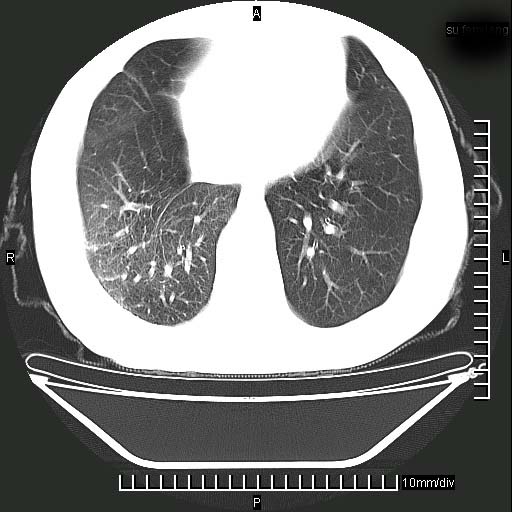

标题: CT24043:胸部增强:男性,60岁

既往肺结核,近10几天,咳嗽,咳痰,右侧胸痛,疼痛较明显,右上肺斑块考虑结核灶胸膜粘连,增强,可惜动脉期没有定好,未见强化,可延迟4分后又见较明显强化,中心见低密度影,如果说结核是边缘强化,可这个灶强化的面积挺大的,让人很挠头。

肺结核、胸膜增厚。

1)两肺继发性肺结核。2)右侧胸膜增厚+少量胸腔积液。